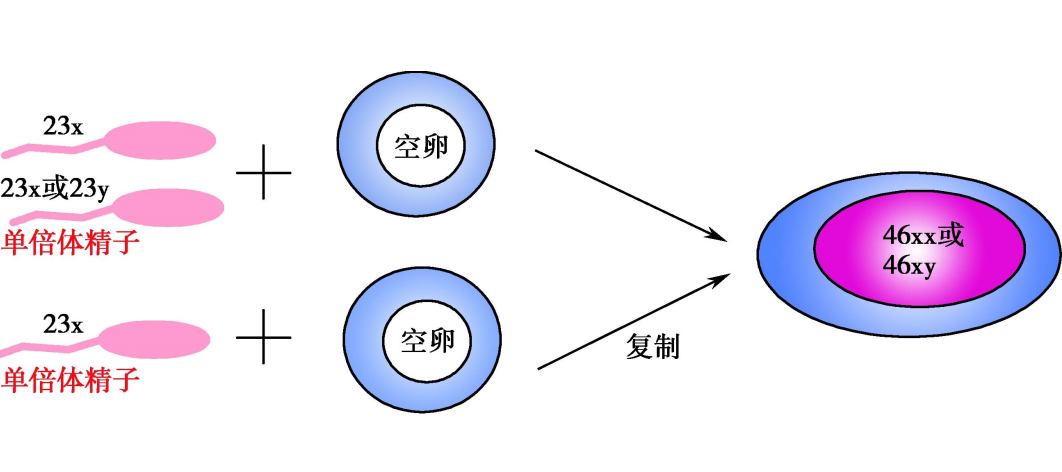

完全性葡萄胎的染色体核型为二倍体,均来自父系,其中90%为46,XX,系由一个细胞核缺如或失活的空卵(enucleate egg)与ー个单倍体精子(23,X)受精,经自身复制为二倍体(46,XX)。另有10%核型为46XY,系由一个空卵被两个单倍体精子(23,X和23,Y)同时受精而成。虽然完全性葡萄胎染色体基因为父系,但其线粒体DNA仍为母系来源。

完全性葡萄胎受精示意图